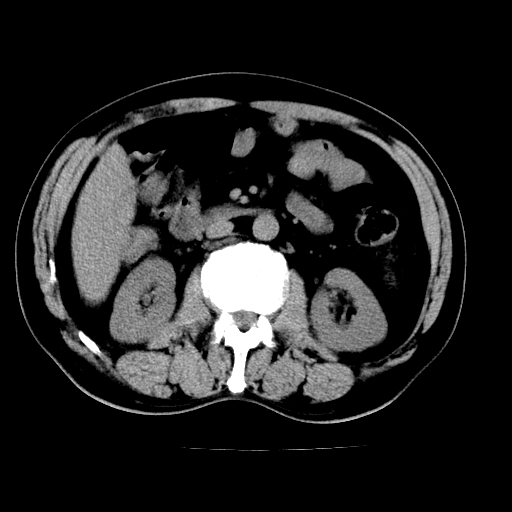

男,66岁,上腹部不适、黄染一周。彩超示:肝左叶占位,肝内胆管扩张,胆总管扩张,胆总管占位?

肝左叶不规则软组织肿块影,边缘不规整邻近肝实质受累分界不清;肝内胆管(左叶)明显扩张成“软藤状”,诊断:肝左叶胆管细胞癌。

肝左叶占位性病变,并胆管扩张,符合胆管细胞癌ct表现,门脉左支受累,左肾囊肿。窗宽太窄了,其他的看不清

左叶胆管细胞癌累及胆总管,门脉左支受侵,慢性胆囊炎胆结石,左肾小囊肿